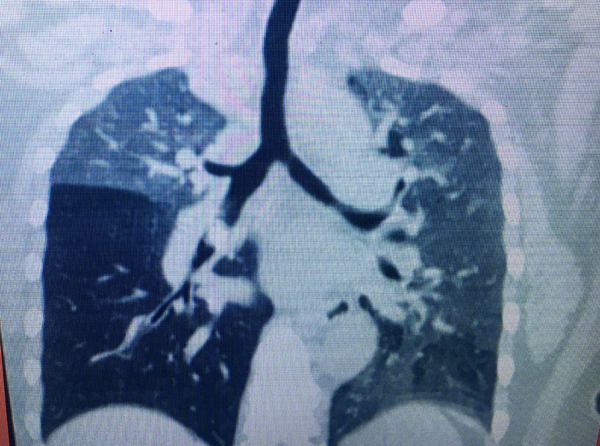

Tại Bệnh viện Tai-Mũi-Họng TP.HCM, bệnh nhân được chỉ định chụp CT scan phổi và phát hiện dị vật phế quản thùy trung gian phổi phải; viêm phổi thùy giữa; thùy dưới phải nên cho nhập viện.

Ảnh cho cho thấy phỏi bị xẹp do dị vật mắc kẹt ở đường thở. Ảnh: Phan Nhơn

“Các trường hợp dị vật đường thở không thể thấy trên phim phổi bình thường, đây là nguyên nhân khiến mảnh xương vịt bị bỏ quên trong đường thở bệnh nhân gần năm trời. Đối với những trường hợp này, theo BS Thủy, chỉ có chụp CT scan hoặc nội soi ống mềm, ống cứng thì mới phát hiện được”, BS Thủy lưu ý.